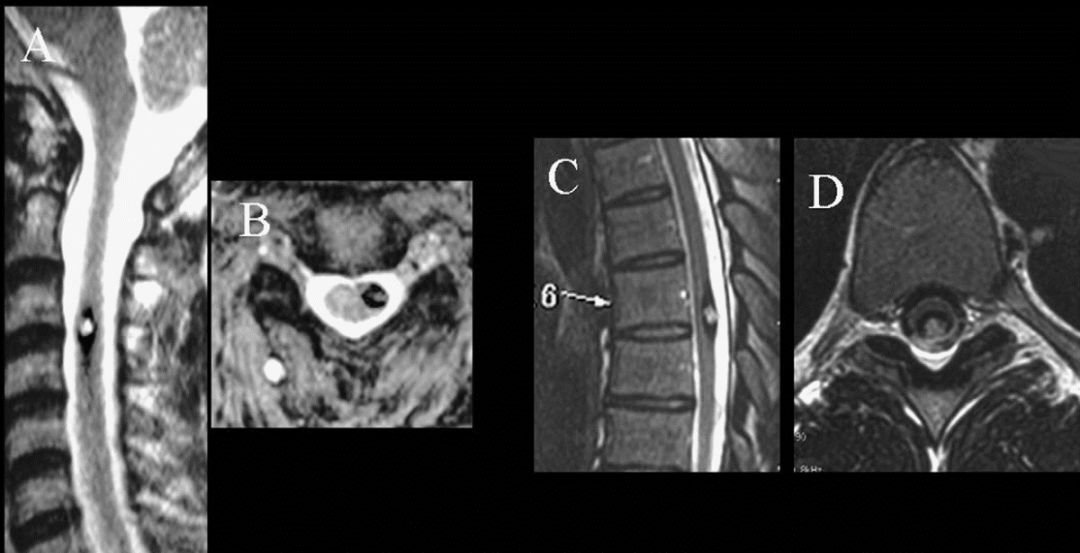

▼术前术后MRI影像对比

辅助检查:胸髓MRI

诊断:胸髓(T6)内占位:海绵状血管瘤;椎管扩大减压术后

2、海绵状血管瘤偏腹侧,位置较深,脊髓表面病灶显现不明显,术中超声辅助定位

(A-C)3D-CT扫描显示位于C1-2水平的髓内CM的术后图像。(B)在术中脊髓表面观察到含铁血黄素染色。(C)完全切除髓内CM,显示髓鞘切开的程度。

(A-C)术中体感诱发电位(SSEP)监测。(A)右侧胫神经的术前SSEP表明术前振幅N40-P50为0.285μV。(B)在硬脑膜开放期间,该振幅上升至1.115μV。(C)在完全清除海绵状畸形后,电压为1.635μV,表明感觉诱发电位好转。